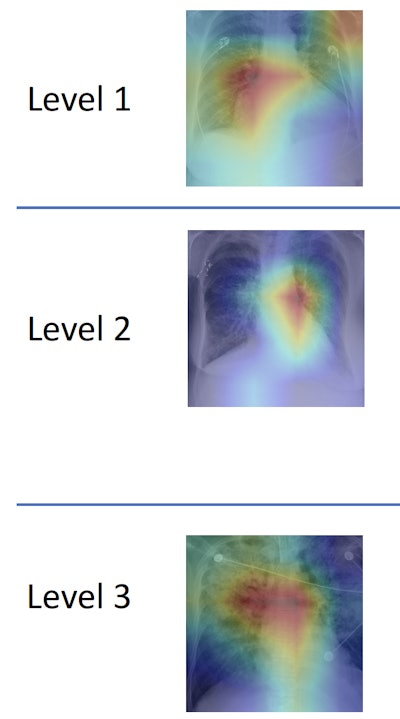

Researchers from the Massachusetts Institute of Technology (MIT), Beth Israel Deaconess Medical Center (BIDMC), and Philips Healthcare found that the algorithm, which categorizes edema on a scale ranging from 0 (normal) to 3 (alveolar edema), was able to identify the correct edema levels as determined by radiologists on more than half of test cases. It also correctly diagnosed level 3 cases 90% of the time.

MIT's machine-learning algorithm quantifies edema on chest x-rays on a scale from 0 (normal) to 3 (alveolar edema). Image courtesy of MIT CSAIL.

MIT's machine-learning algorithm quantifies edema on chest x-rays on a scale from 0 (normal) to 3 (alveolar edema). Image courtesy of MIT CSAIL."The joint image-text representation learning framework incorporates the rich information present in the free-text radiology reports and significantly improves the performance of edema assessment compared to learning from images alone," the authors wrote in their article, published online recently in arXiv.org. "Moreover, our experimental results show that joint representation learning benefits from the large amount of unlabeled image-text data."

Their model also shows the parts of the image and report that corresponded to its prediction. They then assessed the performance of several variants of their model, including one trained using only the labeled images and another trained using both the labeled images and unlabeled images and reports. Performance was compared with classifications of edema levels made by expert radiologists on the test set.